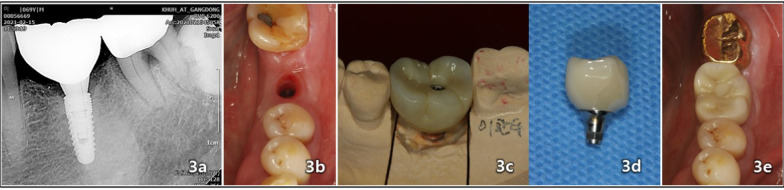

Methods: For control study, total of 23 titanium ASTM F136 grade 23 implants were placed in the edentulous molar area of the mandible. When the Implant Stability Quotient (ISQ) ≥ 70 and insertion torque value (ITV) ≥ 35-50 Ncm at the insertion site, an immediate provisional restoration was connected to the implant within a week after surgery. The definitive restorations were placed 2 months after surgery for all implants. 13 implants were immediately loaded, while 10 implants were conventionally loaded. For comparative study, Radiographs were taken from third years for and then annually for the subsequent eight years to monitor marginal bone loss.

Results: After eight year of implant installation, the average change in vertical bone loss was 0.009 mm (P < 0.001), while the average change in horizontal bone loss 8 year after implant placement was 0.026 mm (P < 0.001). The mean marginal bone loss was < 0.2 mm on average.

Conclusions: In this retrospective study, laser-treated implants exhibit a low rate of bone absorption around the implants.